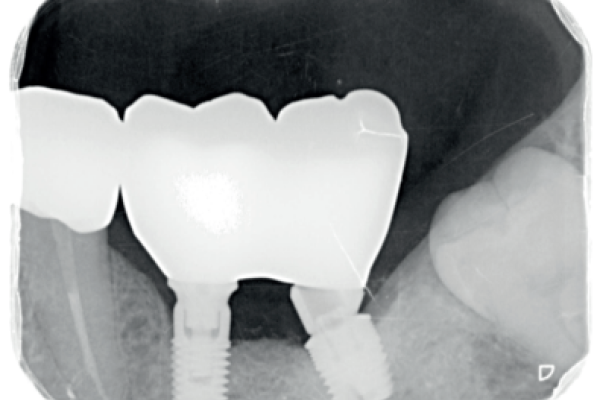

Rehabilitación implantosoportada sobre implantes dentales y cigomáticos en un paciente con radioterapia por un carcinoma adenoide. A propósito de un caso clínico